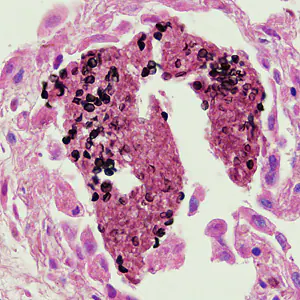

A 35-year-old woman went to her health care provider with complaints of abdominal pain, cramps and diarrhea. She told her doctor that she had recently returned from a business trip to Mexico. Stool was collected in 10% formalin and polyvinyl alcohol (PVA) for routine ova-and-parasite (O&P) examination.